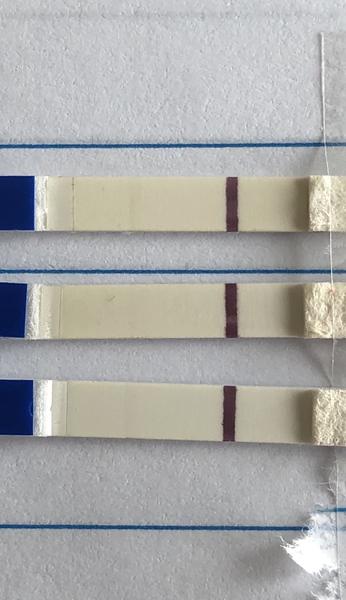

ahojte babule, mam taku otazku...mate skusenost ze pocas 3 dni vam nesilnela druha ciarka na teste ale bola rovnaka???ako duch????

Ahojte baby potrebujem radu dnes som 9-10dpo, od včera mi je zle na žalúdku, vracala som, aj dnes mi je tak isto, tak je mi cudne... A test som si spravila až teraz poobede a nič tam špeciálne nevidím vy áno? Viem ze je to skoro, ale nedalo mi tak som si test spravila a zatiaľ tam nič nie je iba taky ako duch alebo len kanálik 🤔 neviem ťažko povedať..

@tinadeville no tebe to vidno pekne, ja som to mala takto isto voľným okom to lepšie bolo vidno